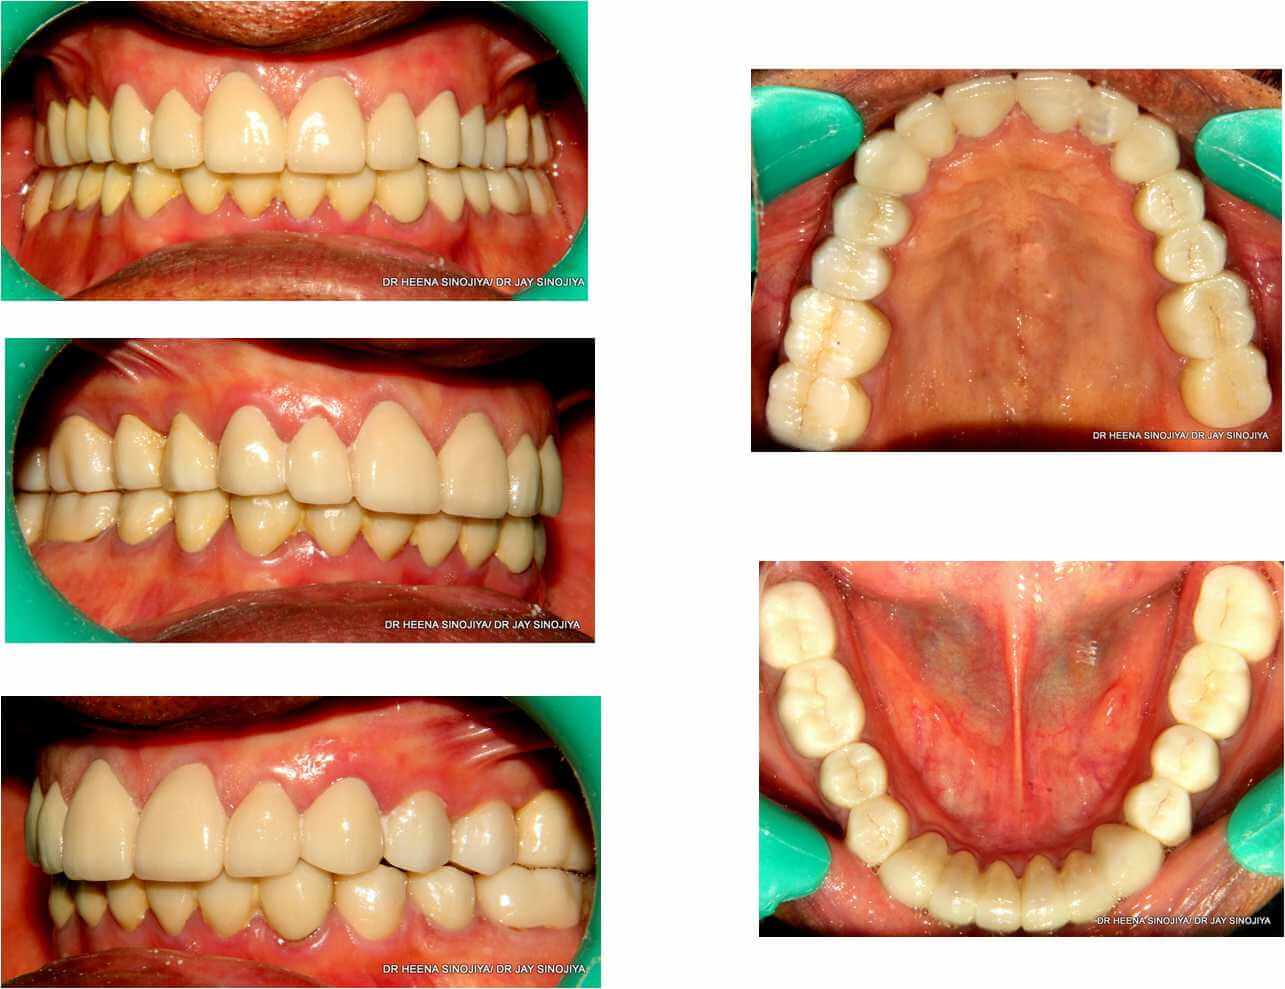

It is the procedure of capping all teeth in the mouth using a systematic approach, step by step procedures and using various instruments. Full mouth rehabilitation creates a smile that is functional, comfortable and beautiful.

We at Lifedent dental hospital use latest instrument that is Corident articulator for preparation of all cap.